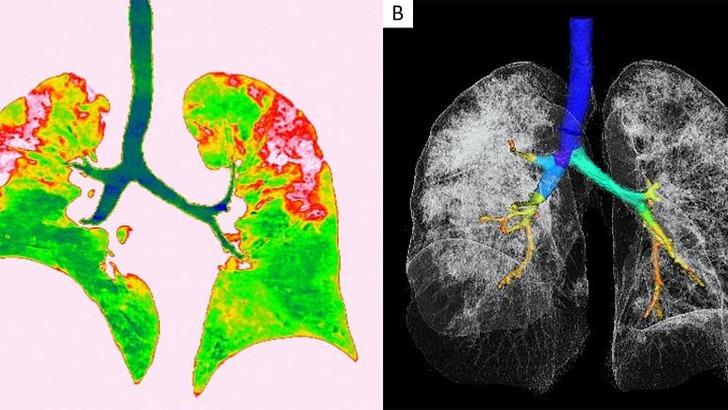

Covid-19'dan kaynaklı zatürre hastası 54 yaşındaki bir kadının transversal ve koronal bilgisayarlı tomografi (BT) görüntülerinde pulmoner lezyonların üst lobda daha yaygın olduğu görülüyor.

Vuhan kentinden döndükten sonra bir hafta boyunca ateşi 38.5 dereceden düşmeyen kadına, nefes darlığı, öksürük ve halsizlik semptomlarıyla hastane yattıktan sonra Covid-19 testi yapıldı. Test sonuçları pozitif çıkan hastaya zatürre teşhisi kondu. Uygulanan tedaviyle söz konusu hastanın semptomlarının hafiflediği rapor edildi.